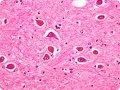

הנחיות חדשות של הקולג' האמריקאי לגסטרואנטרולוגיה בנוגע לאנצפלופתיה כבדית: מה משתנה באבחון, טיפול ומניעה

במרץ 2026, פרסם הקולג' האמריקאי לגסטרואנטרולוגיה הנחיות קליניות חדשות בנושא אנצפלופתיה כבדית בכתב העת האמריקאי לגסטרואנטרולוגיה.